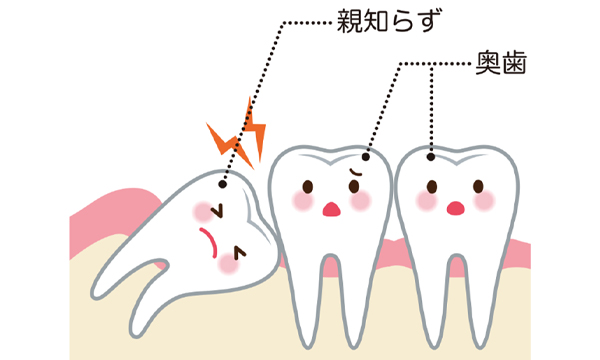

親知らずとは

痛みの原因

頭が少しだけでている状態の時は磨くのが難しいため、汚れが溜まって歯茎が腫れ痛みがでることがあります。

疲れなどで免疫力が下がると症状がでやすくなります。

親知らずによる症状